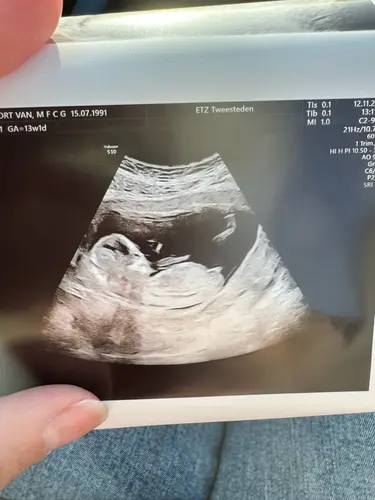

Ik heb deze vanmiddag geplaatst in het andere topic, is met 13+1. Ik heb 1 reactie ontvangen, zijn er nog mensen die een uitspraak kunnen/willen doen op basis van de nub? 🥰

Misschien helpt dit. De echopraktijk voor pretecho’s zegt bij deze echo een meisje omdat de nub vlak loopt aan het einde.